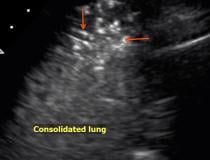

This photo gallery shows the variety of radiological presentations of COVID-19 (SARS-CoV-2) in medical imaging, including computed tomography (CT), radiograph X-rays, ultrasound, echocardiograms and magnetic resonance imaging (MRI). The radiology images show examples of typical COVID pneumonia in the lungs and the numerous complications the virus causes in the body in multiple organs, including the brain, kidneys, heart, abdomen and vascular system.

Ultrasound, especially hand-held ultrasound imaging devices, have become a primary imaging modality for novel coronavirus because of the ease to bag the device and sterilize it after use. CT and mobile X-ray systems are also used as front-line imaging systems for COVID-positive or suspected COVID patients.